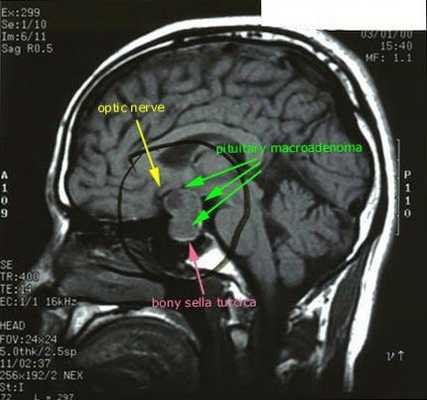

- МРТ области турецкого седла с контрастированием;

![МРТ гипофиза]()

При БИК в 80-85% случаев выявляют микроаденому гипофиза (опухоль до 10 мм), у остальных 15-20% — макроаденому (доброкачественное новообразование от 10 мм). [7]